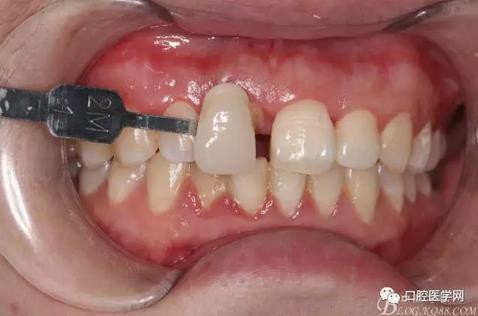

牙冠延長(zhǎng)術(shù)后6周復(fù)診牙齦齦緣形態(tài)恢復(fù)良好,齦乳頭有些欠缺,患者著急永久修復(fù)。

戴牙